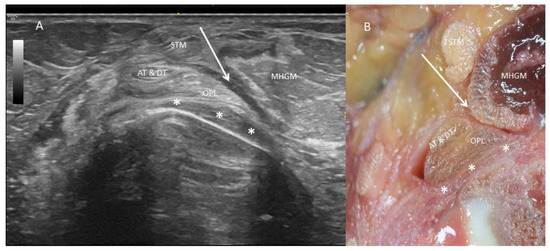

3.1. Ultrasound Study

3.2. Anatomical Study